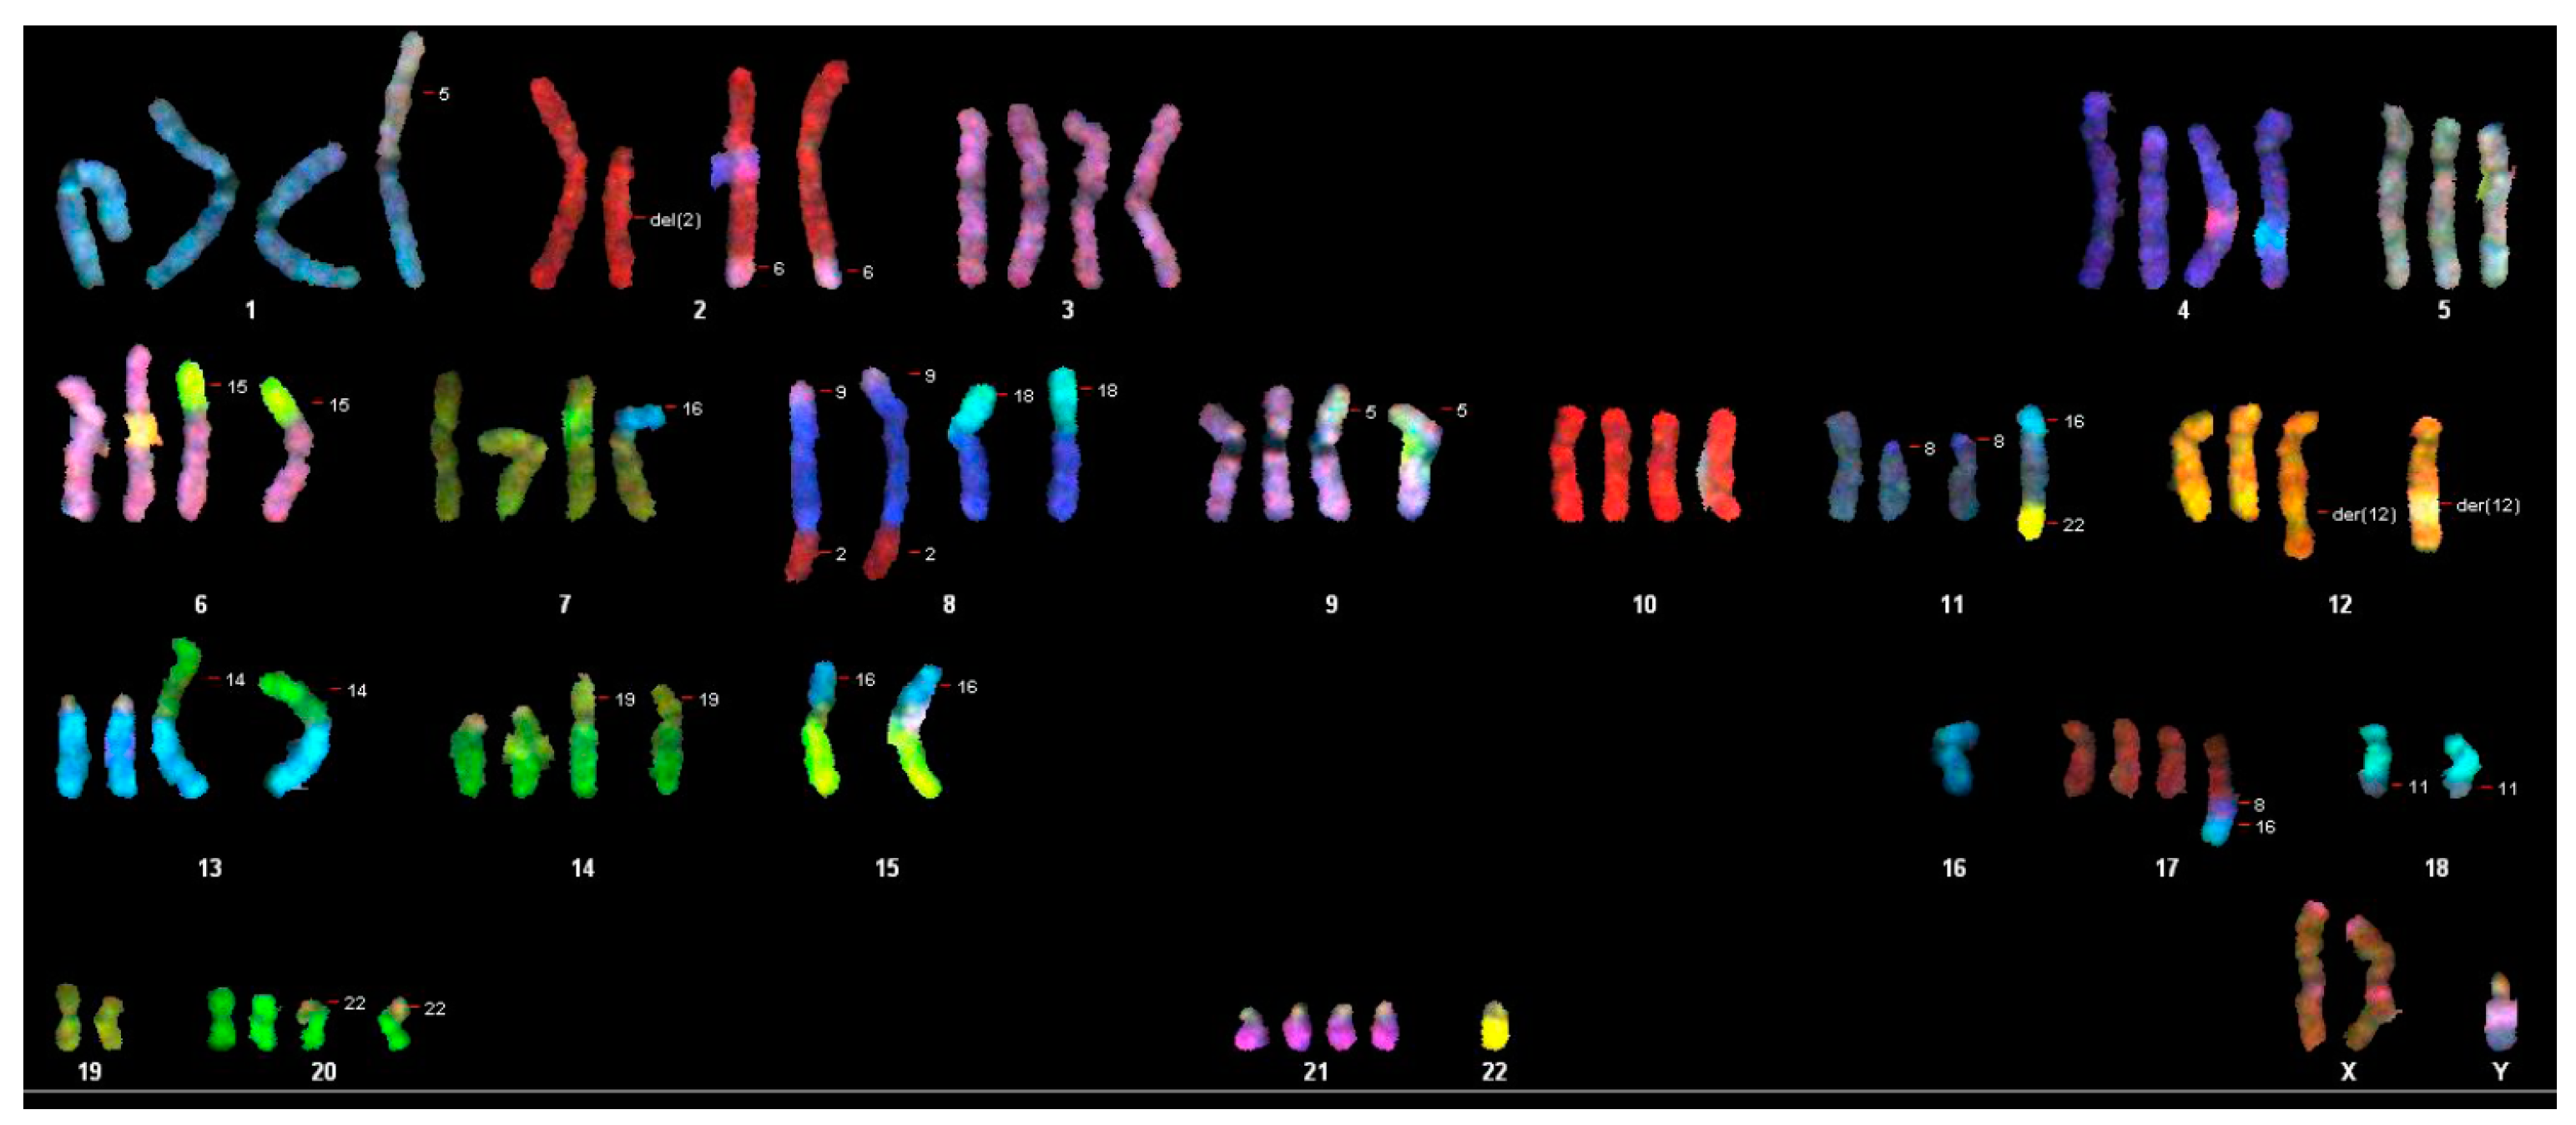

3.2. Cytogenic Characteristics and DNA Profile of the WG-59 Cell Line

| Composite Karyotype SKY: |

|---|

| 70-91,XX,-Y[11],-Y[12],der(2)t(2;6)x2[11],-3[3],-4[4],der(6)t(6;15)[2],der(6)t(6;15der(8)t(9;8;2)x2[12],der(8)t(8;18)[7],der(8)t(8;18)x2[5],-9[4],+9[2],der(9)t(5;9)[5],der(9)t(5;9)x2[6],-10[4],-11[3],der(11)t(8;11)x2[7],der(12)t(5;12)x2[4],-13[7],-13[3],rob(13;14)[4],rob(13;14)x2[7],-14[5],-14[7],der(14)t(14,19)[4],der(14)t(14,19)x2[4],-15[12],-15[12], der(15)t(15;16)x2[9],-16[5], del(16)x2[8],der(16)t(16;20)x2[3],-17[4],-18[11],-18[7],der(18)t(5;18)[2],der(18)t(11;18)x2[7],-19[2]-19[10],-20[3],-20[2],der(20)t(20;22)x2[9],-21[3],-22[12],-22[12][cp12] |